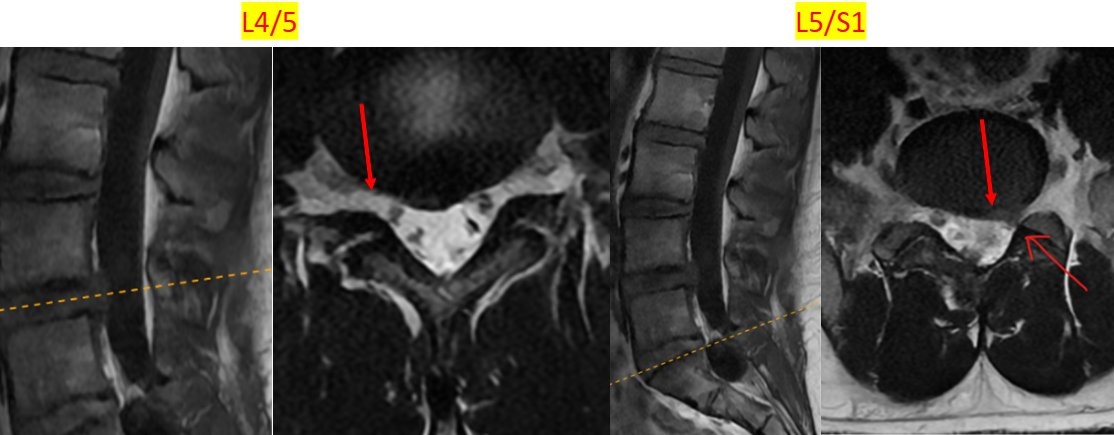

| Hình ảnh chụp MRI cột sống thắt lưng cho thấy tình trạng bất thường vùng đĩa đệm. |

Kết quả chụp cộng hưởng từ cho thấy đĩa đệm L5/S1 bị phồng, chèn ép rễ thần kinh bên trái. Chẩn đoán xác định, bệnh nhân mắc viêm dây chằng liên mỏm gai, phồng đĩa đệm L4/5, L5/S1 có chèn ép rễ thần kinh và nang Tarlov vùng cột sống thắt lưng.